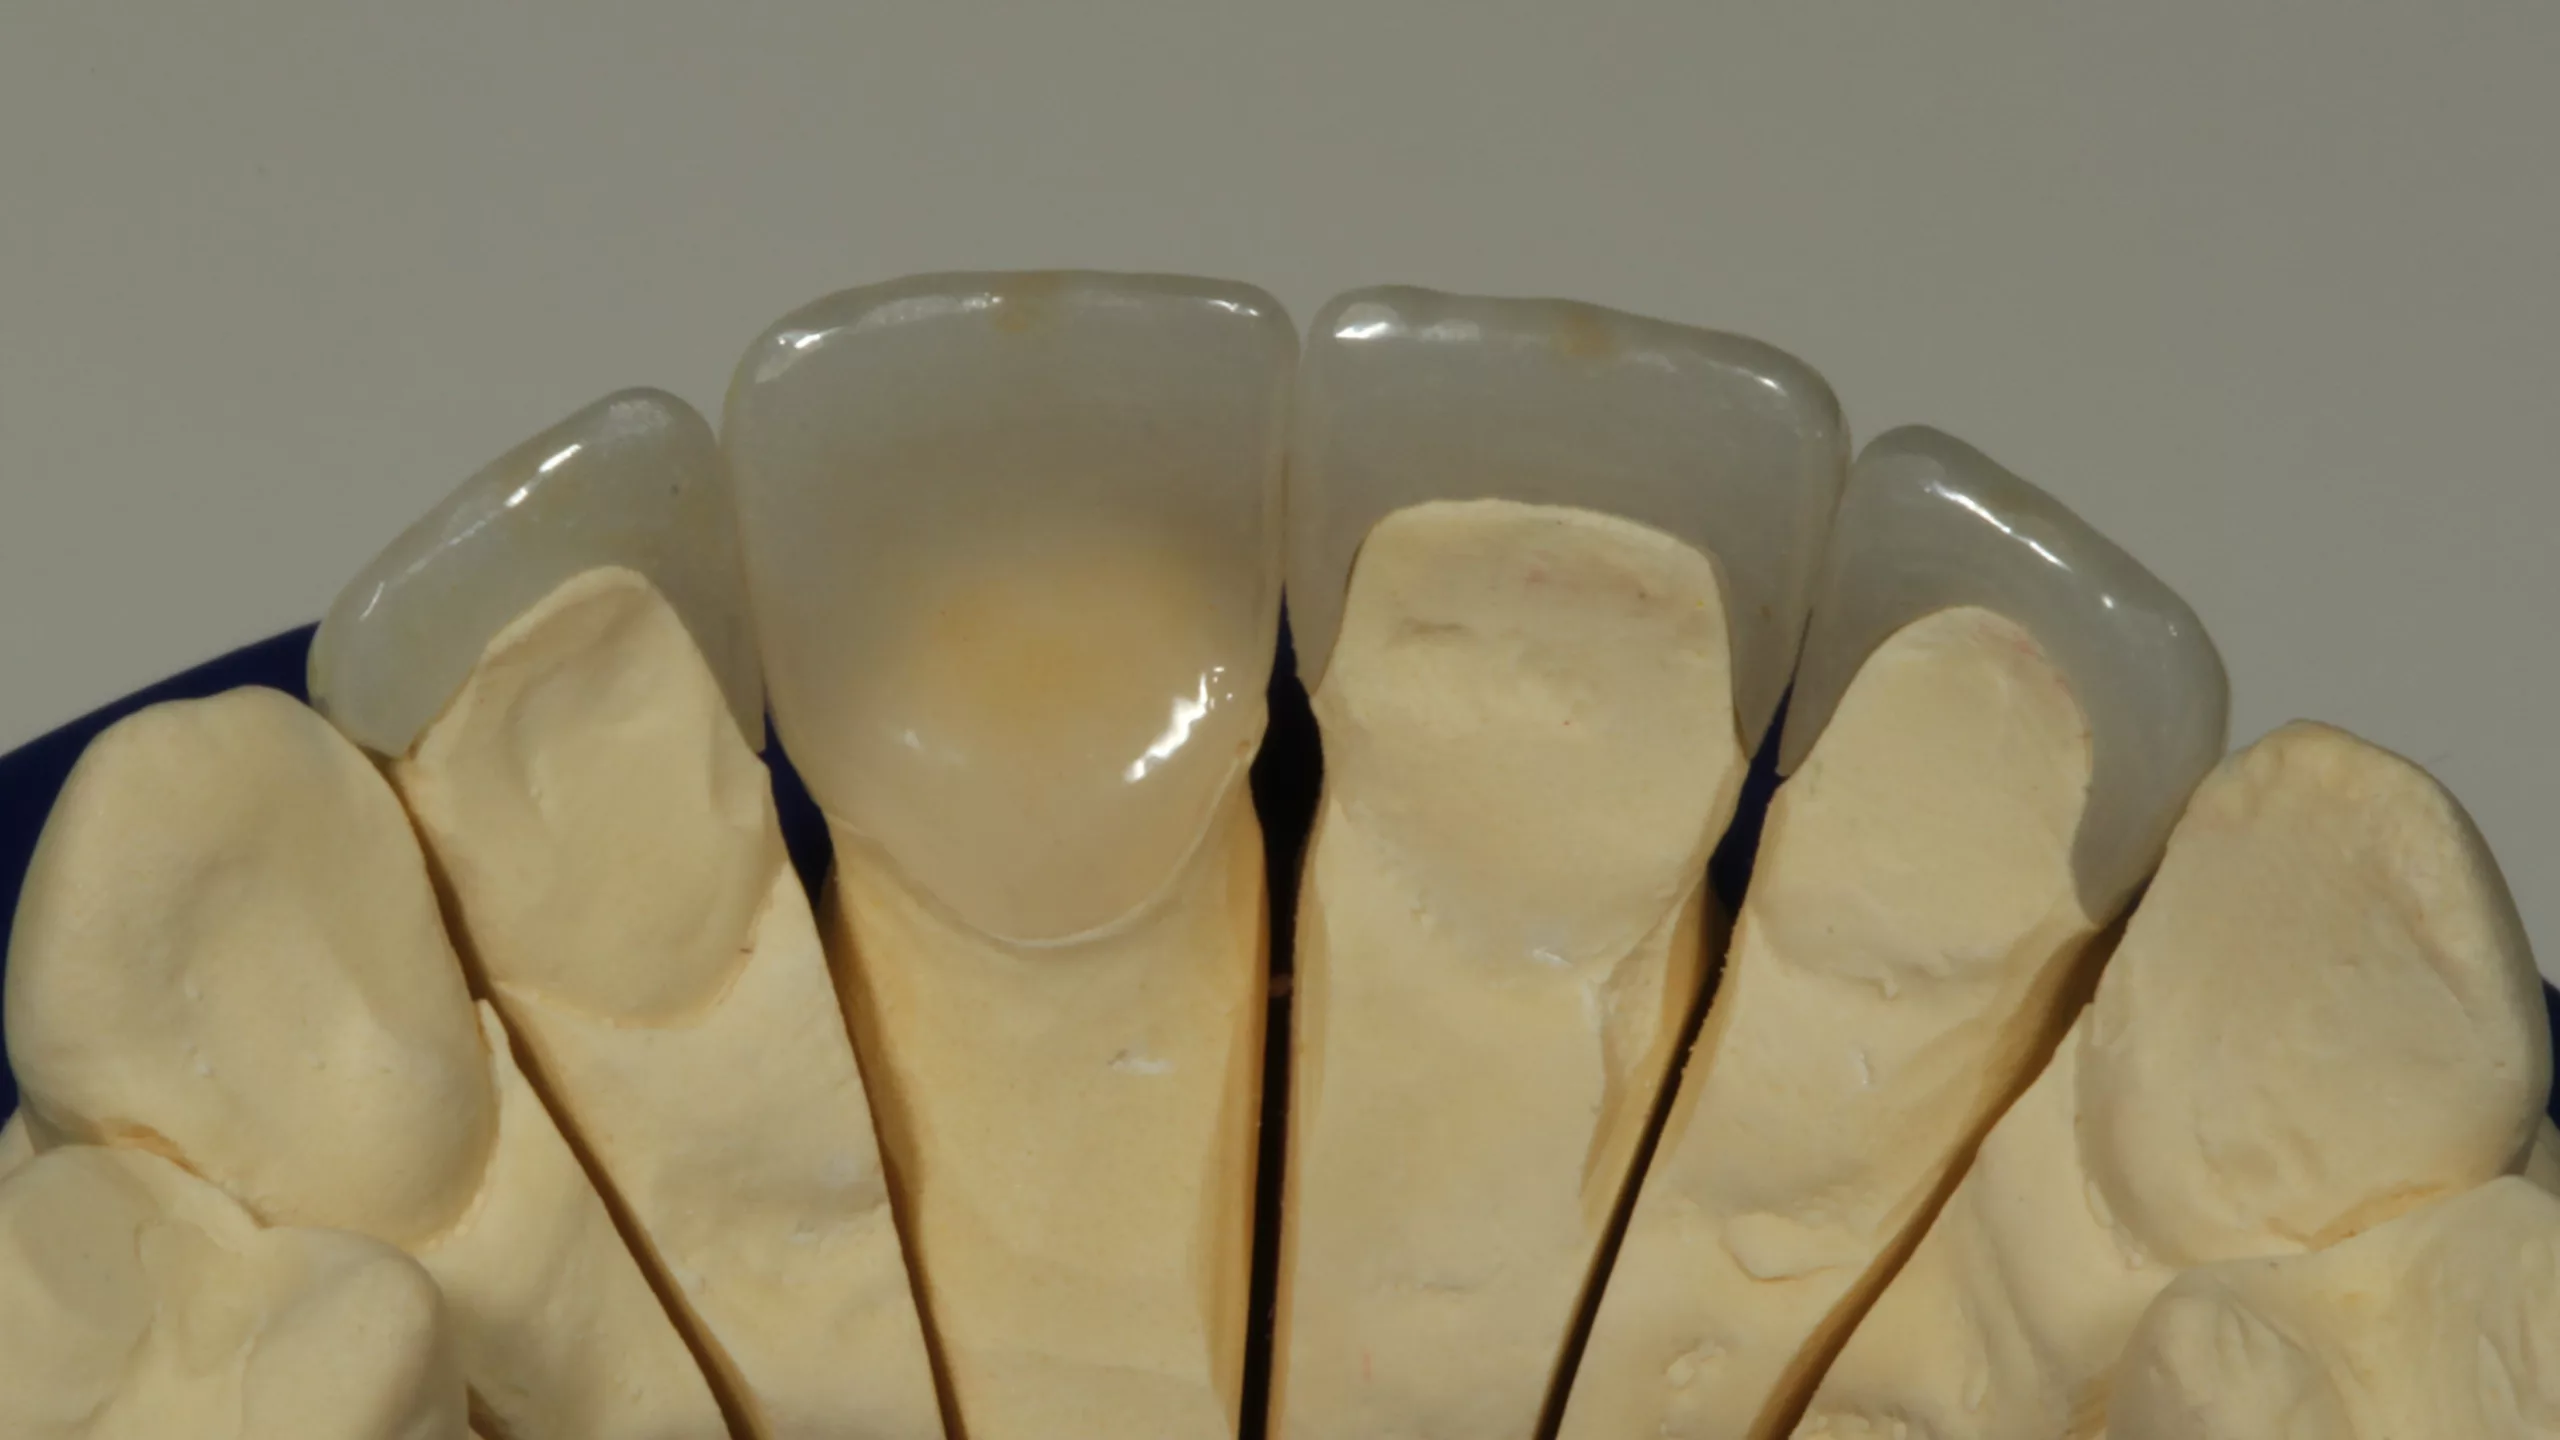

Fall 1: Befestigung von 2 Lithiumdisilikat-Teilkronen

Bei der 42-jährigen ärztlichen Kollegin waren insuffiziente, größere Kompositrestaurationen mit z.T. Höckerersatz an den Zähnen 46 und 47 auszutauschen. Die Wahl fiel aus ästhetischen Gründen auf eine Lithiumdisilikatkeramik (IPS e.max Press, Ivoclar Vivadent). Die Farbbestimmung erfolgte chairside durch einen der praxiseigenen Zahntechnikermeister. Die Abbildung 1 zeigt die fertiggestellte Laborarbeit auf dem Arbeitsmodell. Die entscheidende Vorbehandlung der Keramik ist im Anschluss an die Einprobe die Reinigung der Keramik mit Ivoclean oder Phosphorsäuregel [10] und die anschließende Flusssäurekonditionierung. Die 5%ige Flusssäure stellt nach wie vor die am besten bewährte Vorbehandlungsmethode für glasbasierte Keramiken dar [1,12,14, 36,51,61,73]. Eine Meta-Analyse aus dem Jahr 2015 bestätigt dies [69].